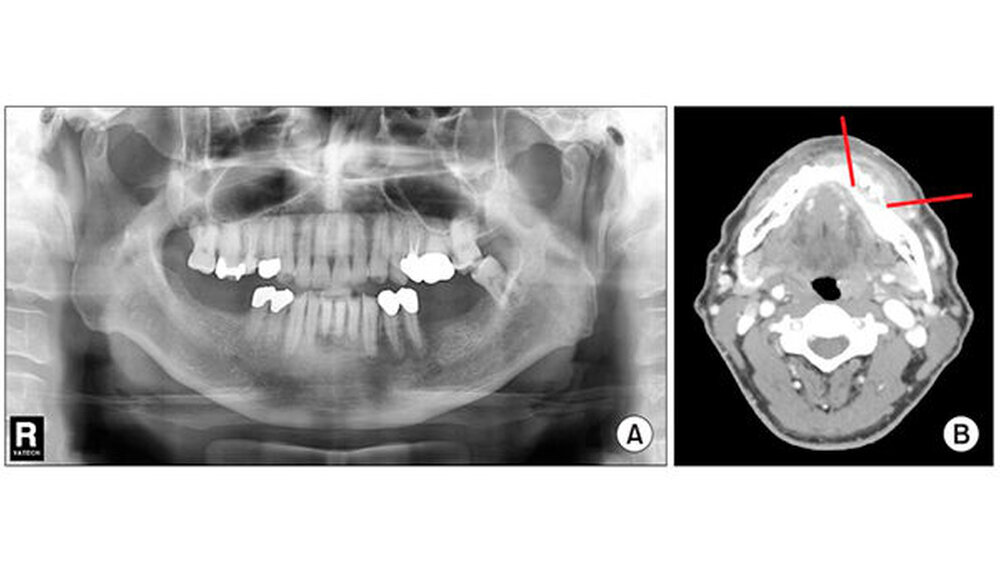

Ein 64-jähriger Mann stellte sich am 16. Dezember 2013 am Institut für Kiefer- und Gesichtschirurgie des Pusan National University Hospitals in Busan (Korea) vor. Er klagte über starke Schmerzen - sein Alveolarknochen des linken Unterkiefers lag komplett frei. Fünf Wochen zuvor hatte er eine Hautveränderung im linken Unterkieferbereich bemerkt, woraufhin ihm sein Hautarzt ein antivirales Mittel verschrieb. (Abb. 1 A). Davon abgesehen hatte er keine ernsten Beschwerden.

Die intraorale Untersuchung zeigte einen freiliegenden Alveolarknochen in den Bereichen 34, 35 sowie eine Lockerung dritten Grades der Zähne 31 bis 35. (Abb. 1 B) Röntgenaufnahmen offenbarten eine diffuse und unregelmäßige strahlendurchlässige Knochenläsion im linken Unterkiefer sowie eine Weichteilschwellung mit niedriger Dichte. (Abb. 2) Mithilfe einer Biopsie stellten die Zahnärzte akute und chronische Entzündungen fest. Der Patient hatte weder Rezepte für Medikamente verschrieben bekommen, die den Knochenstoffwechsel beeinflussen, noch hatte er jemals eine Strahlentherapie erhalten.